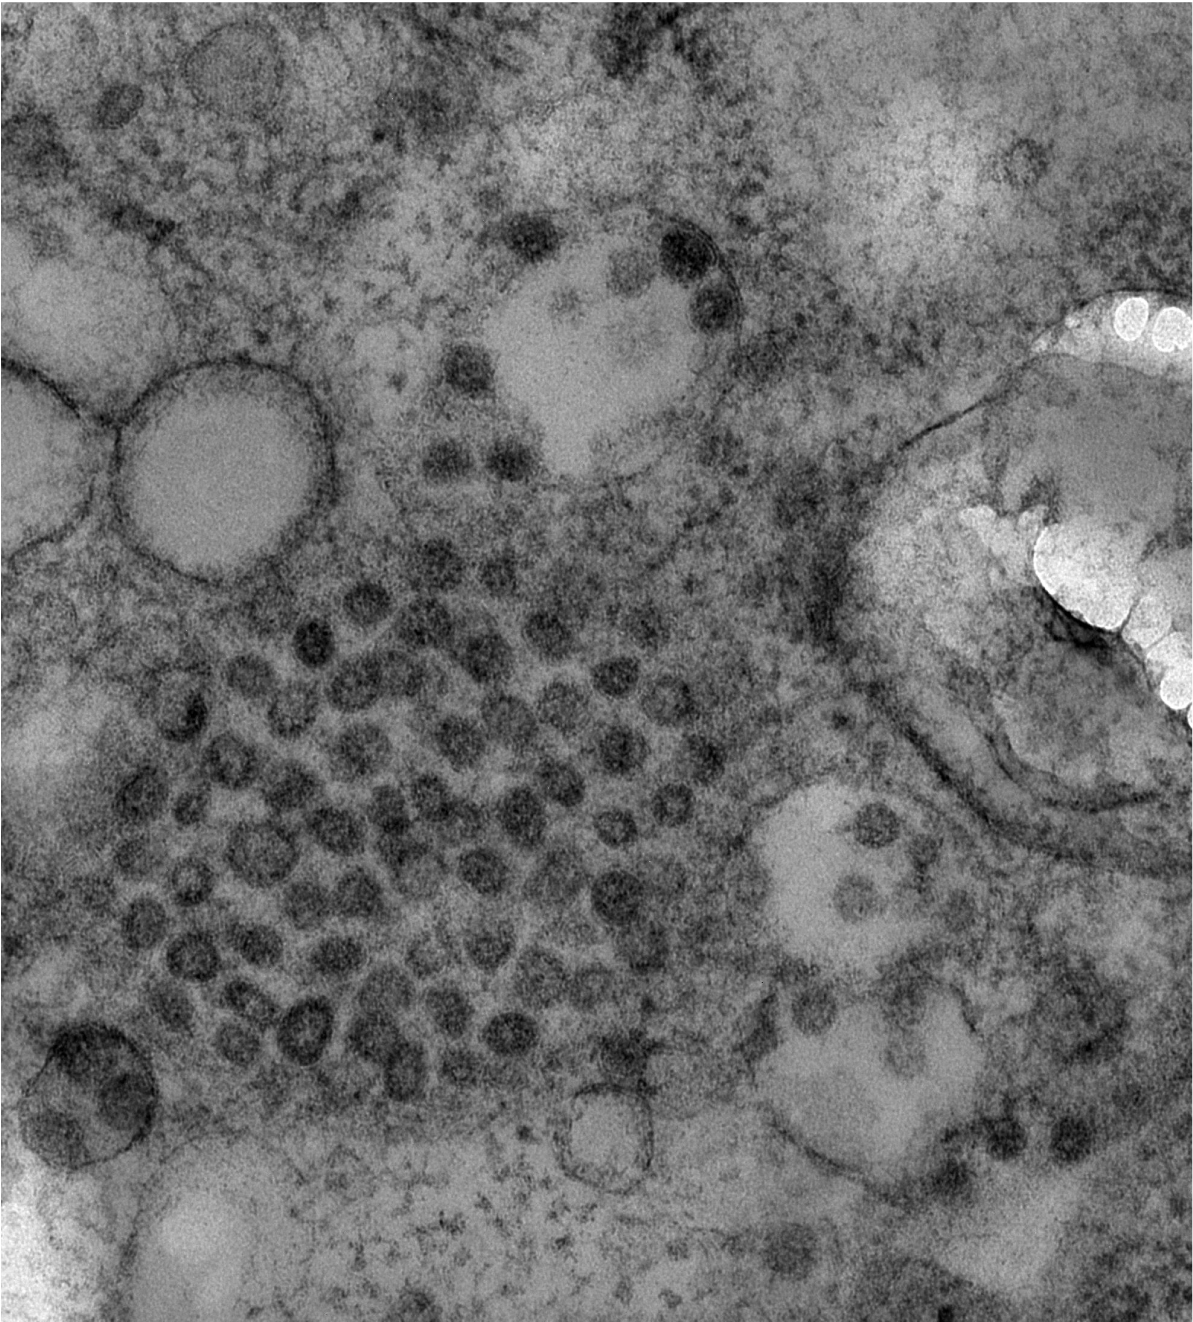

Bild 2: SARS-CoV-2 Partikel in einer Zelle eines Nierenorganoids.